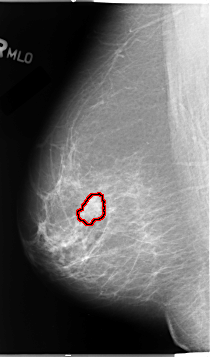

B_3068_1.RIGHT_MLO

RIGHT_MLO LINES 4632 PIXELS_PER_LINE 2728 BITS_PER_PIXEL 12 RESOLUTION 50 OVERLAY

FILE: B_3068_1.RIGHT_MLO.OVERLAY

TOTAL_ABNORMALITIES 1

ABNORMALITY 1

LESION_TYPE MASS SHAPE IRREGULAR MARGINS MICROLOBULATED-ILL_DEFINED

ASSESSMENT 4

SUBTLETY 4

PATHOLOGY MALIGNANT

TOTAL_OUTLINES 1

BOUNDARY